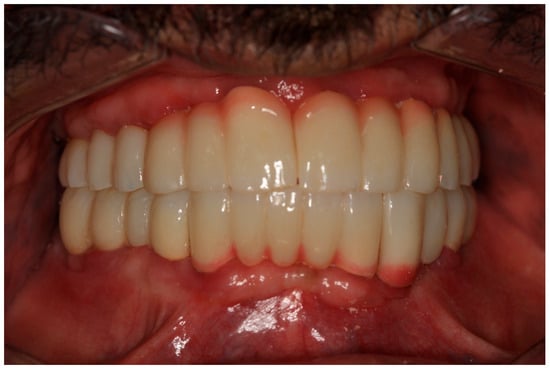

Figure 14. The final prostheses.

The restoration plan involved placing a bridge that connects the central incisors to the canines, along with an additional bridge spanning the first premolar to the first molar on each side of the maxillary arch. In the mandibular arch, the plan included three bridges: one connecting the lateral incisors bilaterally and another bridging the canines to the second premolars and first molars on each side (Figure 14 and Figure 15). Placing was confirmed using Panoramic radiographs obtained using the PantOs DG XP panoramic dental X-ray system (Fona S.r.l., Assago, Italy; CE 0051). The unit operates on a 230 V, 50/60 Hz input line with an 8 A fuse. Standard panoramic exposure parameters were applied (90 kVp, 10 mA, exposure time 14 s) following the manufacturer’s safety recommendations. A trained radiology technician performed all scans, and patient positioning was standardized using the built-in cephalostat support and light-beam alignment to ensure reproducibility of serial images.

2.6. Sixth Visit